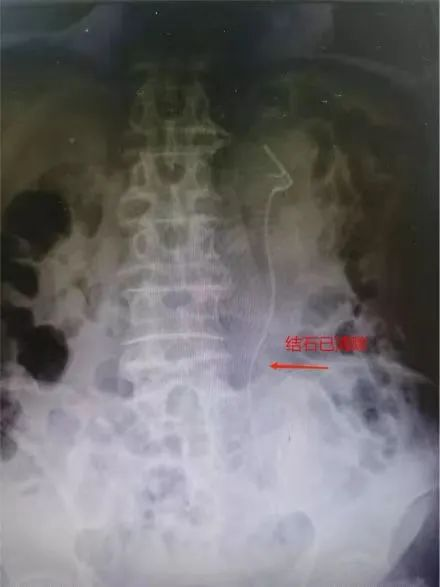

如果把人体比作一个房间,泌尿系统就是一个“下水管道”,其中包括肾脏、输尿管、膀胱以及尿道这几个重要器官,而“尿路结石”就是“下水管道”中的某个部位出现了石头。如果结石长在了输尿管,哪怕只有半公分,都会让人痛不欲生。而来自惠州83岁的翁伯,就因“腰痛”在惠州某医院检查彩超时发现左输尿管上段结石并左肾积水,当地医院建议保守治疗。但保守的治疗效果欠佳,反复的腰痛,严重影响翁伯的生活质量。经患者及其家属多方打听,了解到我院毕学成主任是省内外知名泌尿外科专家,尤其在微创泌尿手术方面造诣颇深,便慕名前来该院泌尿外科就诊。毕学成获悉病情后带领泌尿外科团队认真研究分析病情,经过充分的术前评估后,为患者实施了微创激光碎石手术,成功打通了“下水道”!术后复查结石清除干净,彻底解除了翁伯的“腰痛”问题。出院时,翁伯激动地说:“水龙头开关终于打开了,解决了我多年的困扰,真心为你们医院高超的医疗技术和优质的服务点赞。”

病人术后X光,显示结石已清除